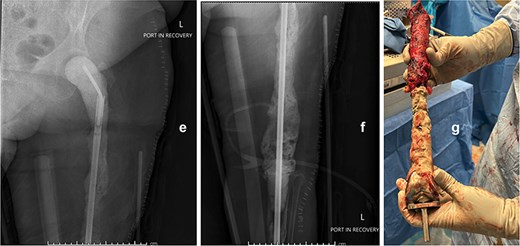

Following implant removal and thorough debridement, a custom total femur antibiotic spacer was fashioned using an Ilizarovrod embedded in antibiotic-loaded cement, coupled to a fully cement-coated fusion nail (Fig. 2). This construct extended from the acetabulum to the tibia, preserving limb length and joint space. The patient was kept non-weight-bearing and initiated on intravenous cefazolin. The postoperative course was uneventful, with no immediate complications.

Intraoperative anteroposterior radiographs (e and f) after stage one, demonstrating a custom antibiotic-loaded total femur spacer constructed using an Ilizarov rod embedded in antibiotic cement and a fully cement-coated fusion nail extending from the acetabulum to the tibia. The resected right femoral implant is grossly visualized (g) prior to spacer placement.